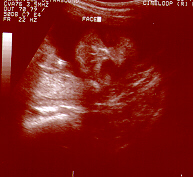

Jolie's Profile

Jolie's Profile with her head on the right.